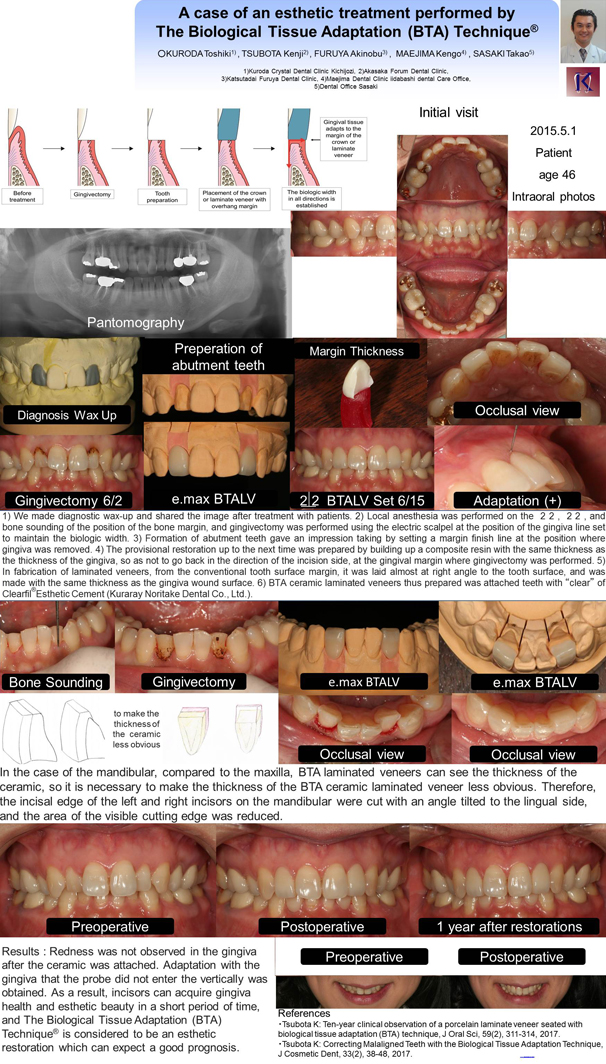

• 2017年 第10回 国際歯科審美学会世界大会(IFED)ポスター発表

2017年 富山で開催された、第10回国際歯科審美学会世界大会(IFED)ポスター発表

テーマは「(BTA)TechniqueRを用いて審美的歯科治療した1症例」

前歯の暗い感じを気にして、4ヵ月後の海外への転勤までに見た目を綺麗にしたいと来院された前歯の位置関係を、(BTA)TechniqueRを用いて、殆ど削らずに、来院回数2回で、審美的なセラミックを装着し、歯肉の健康と審美性を得ることができた。The Biological Tissue Adaptation (BTA) TechniqueRは良好な予後が期待できる審美的修復と考えられる。この1症例を大判のポスターを用いて学会発表致しました。

テーマ ; A case of an esthetic treatment performed by The Biological Tissue Adaptation (BTA) TechniqueR

発表演者 ; Kuroda Toshiki

Patients : The patient was a woman who cared about the dark feeling of the incisors. It was the main complaint that she wanted to make beautiful appearance before the transfer to overseas after 4 months. The case is due to lingual dislocation of incisors

Treatment Planning and method : Surgical operations such as crown lengthning or orthodontic treatment become necessary in order to prepare incongruity of lingual dislocation and gingival margin. This time, because the time period is limited, they can not be applied. Therefore, esthetic treatment performed by the Biological Tissue Adaptation (BTA) TechniqueR was applied.

Results of Treatment and Conclusion : Redness was not observed in the gingiva after the ceramic was attached. Adaptation with the gingiva that the probe did not enter the vertically was obtained. As a result, incisors can acquire gingiva health and esthetic beauty in a short period of time, and The Biological Tissue Adaptation (BTA) TechniqueR is considered to be an esthetic restoration which can expect a good prognosis. We will continue to observe this case.